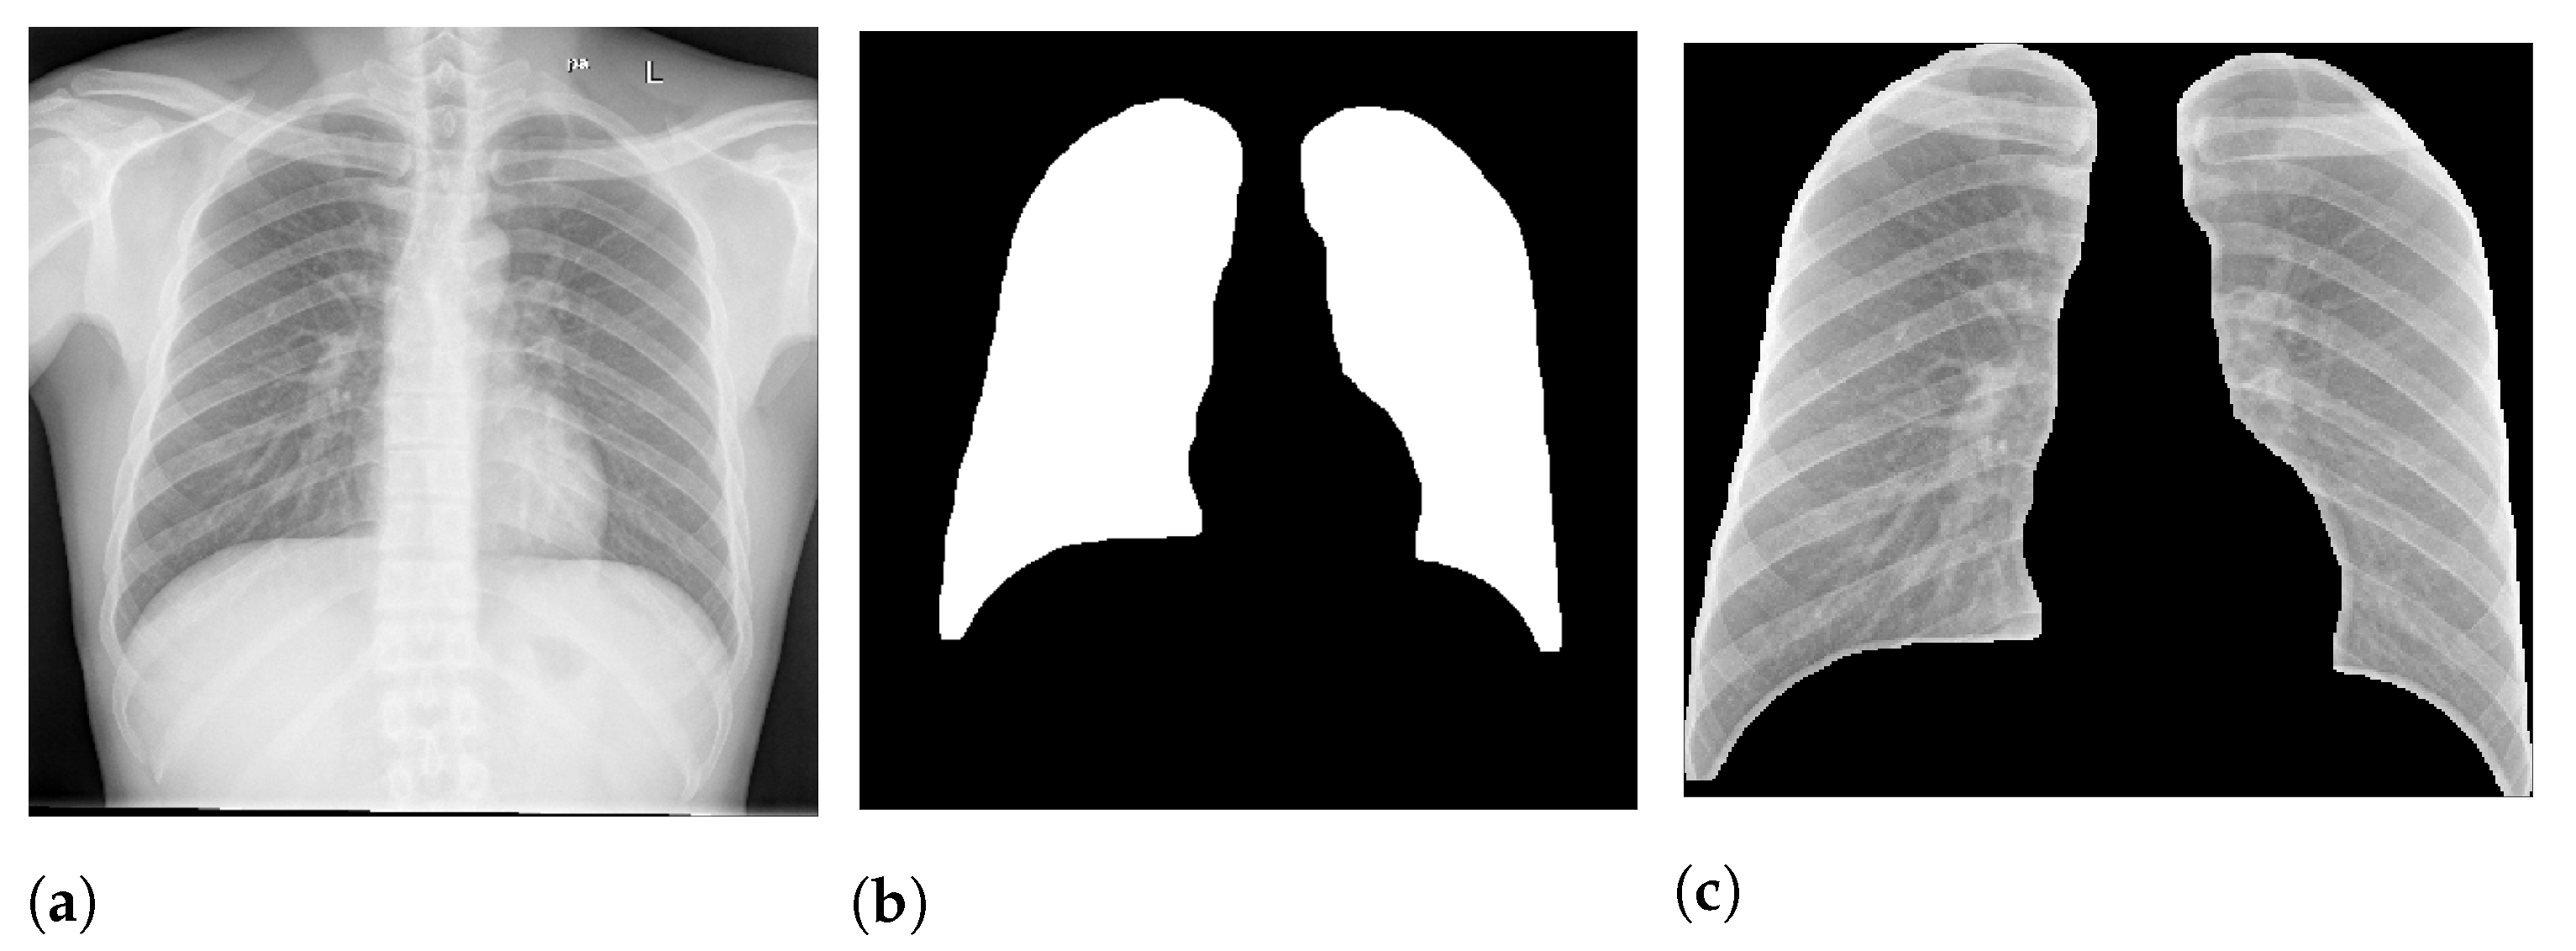

Figure 2 presents an example of lung segmentation.

We expect that the models using segmented images rely on information in the lung area rather than background information, i.e., an increase in the model reliability and prediction quality in a real-world scenario. For example, if a model is trained to predict lung opacity, it must use lung area information. Otherwise, it is not identifying opacity but something else.

Figure 2 shows an example of this process.